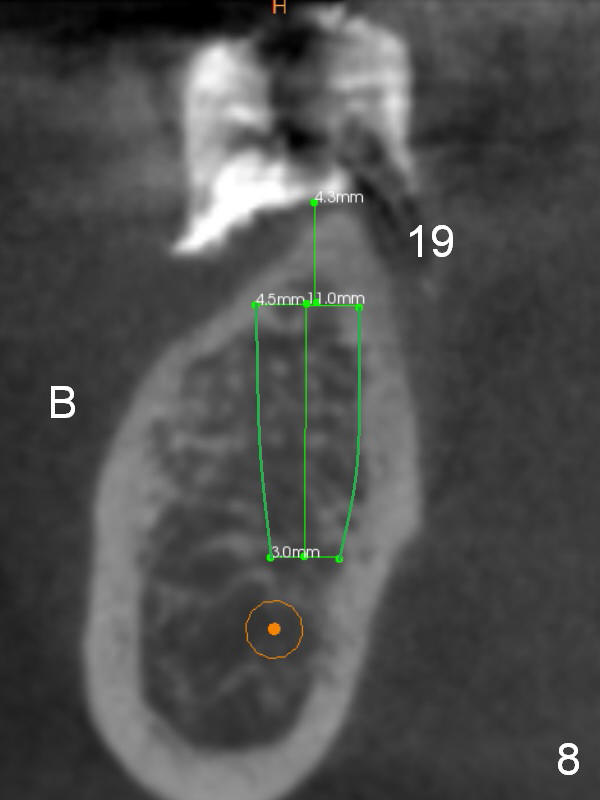

The lady has taken Fosamax for osteoporosis several years. The medicine may cause osteonecrosis. CBCT study does not show sign of osteonecrosis apparently (Fig.7-9). Since the ridge at #19 is narrow (Fig.8), it is reasonable to have a premolar there after ridge trimming.